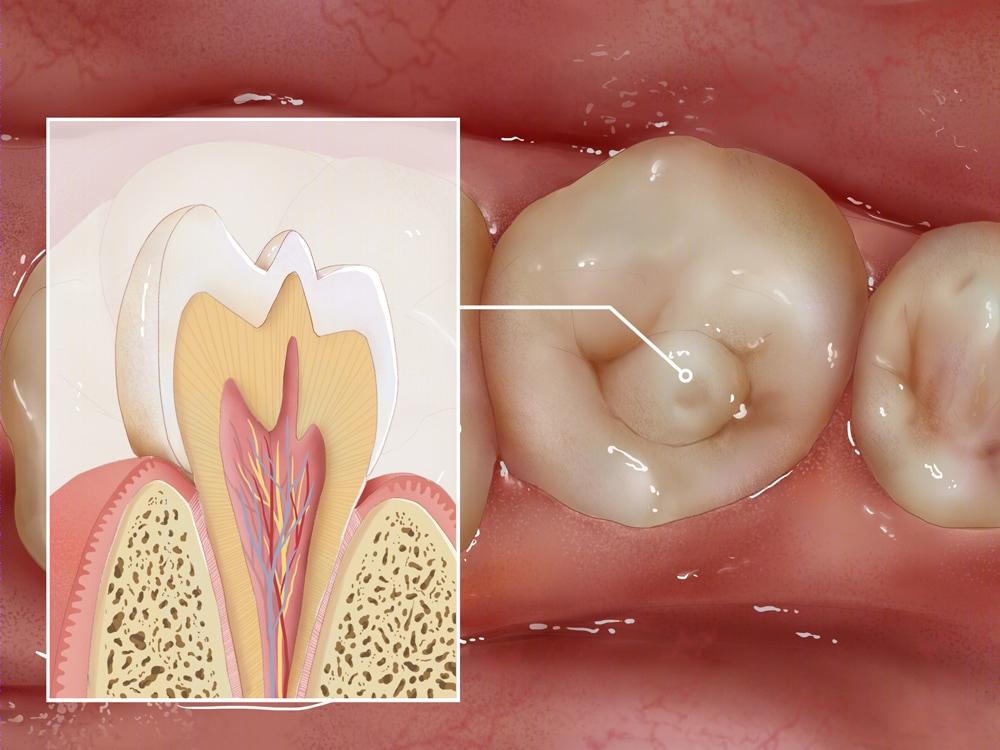

畸形中央尖又称牙外突(Dens evaginatus,DE)是一种牙体形态发育畸形,是指在牙齿牙合面中央窝处,或接近中央窝的颊尖三角嵴上出现的突起的圆锥形牙尖。畸形中央尖好发于前磨牙,其中以下颌第二前磨牙最为常见,常为左右对称性发生,恒牙多见。

畸形中央尖完好无损时,表现为牙齿颌面中央凸起的小牙尖。当被逐渐被磨损后,表现为圆形或椭圆形黑环,中央有浅黄色或褐色牙本质,可能伴有牙齿敏感的症状。

进一步被折断后,会引起牙髓炎或根尖周炎,表现为牙齿疼痛,不敢咬物。对于年轻恒牙而言,牙髓的感染坏死,将影响牙根的继续发育。